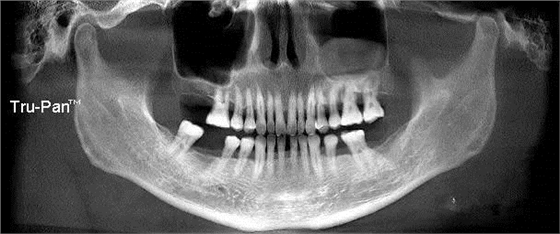

第四圖:上頜竇發(fā)育不足,上頜竇底骨高度充裕,通常頰側(cè)骨壁超級厚,看下圖2.臨床上種植常不需要提升措施。(如需提升,切記頰側(cè)骨厚度過大,開窗的困難性劇增)